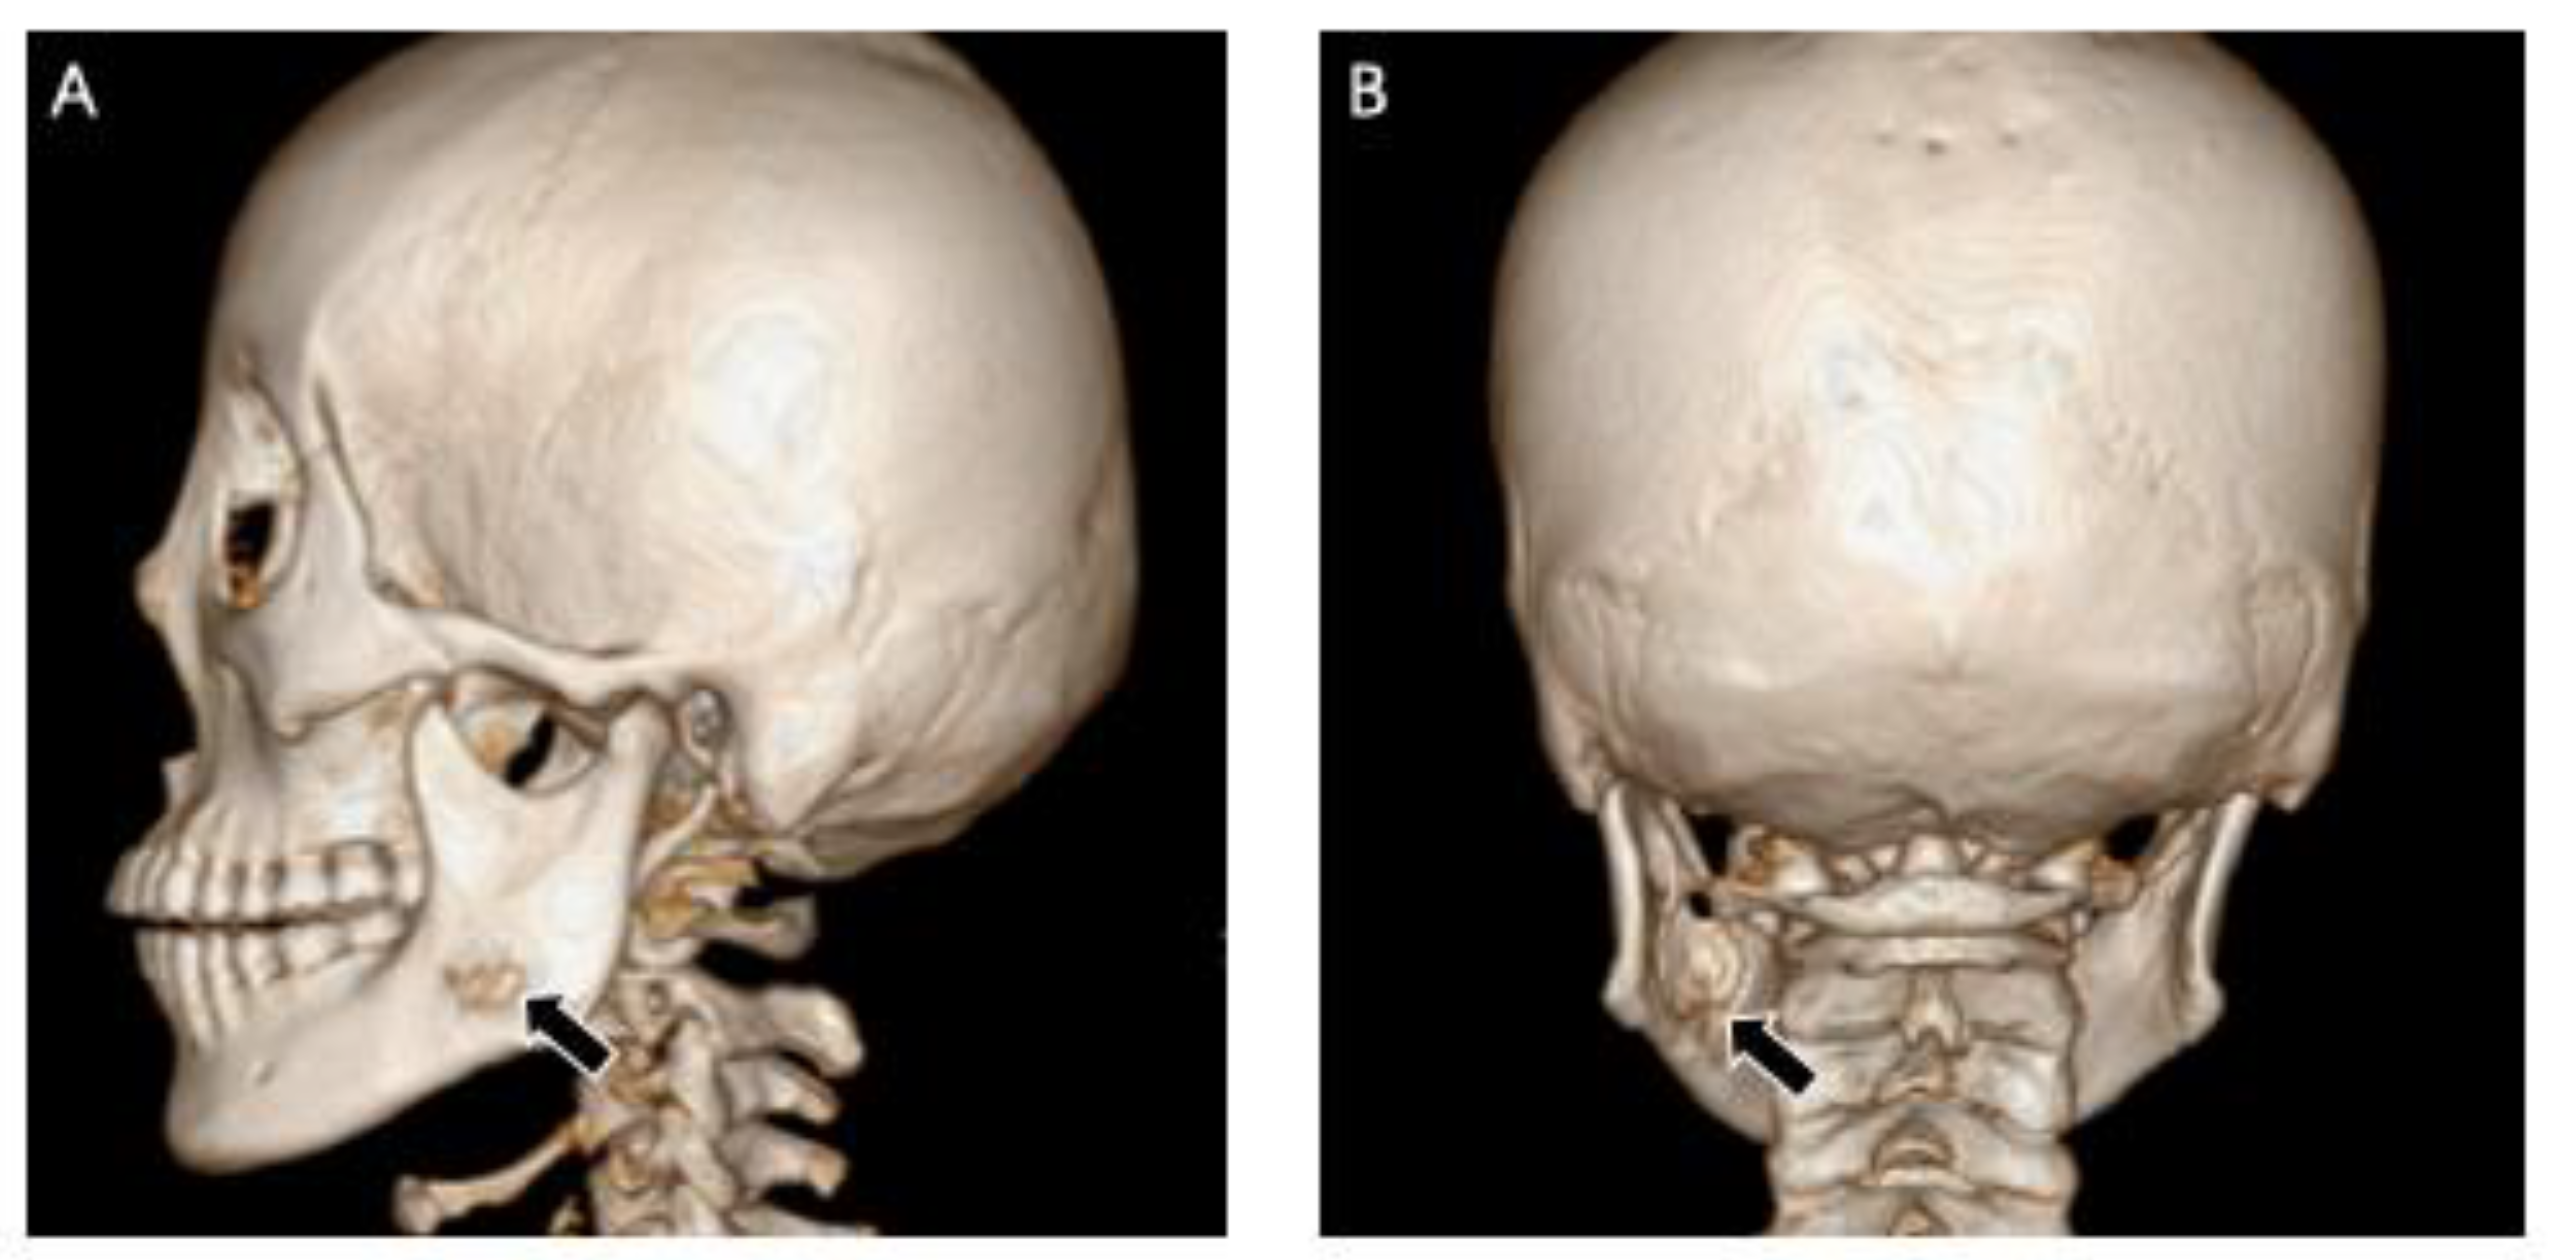

2.1. Case 1

2.2. Case 2